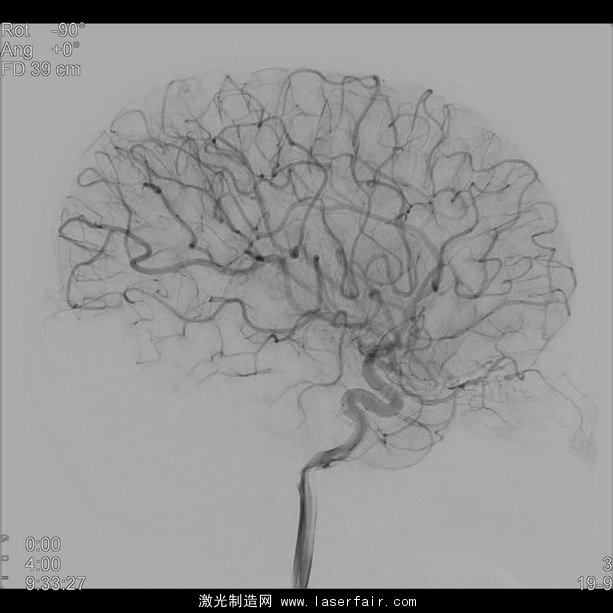

神經放射學是放射學的分支之一,包含了大腦、頭頸和脊椎的診斷和微創治療。這些療法需要插入導管,必須在實時圖像引導的幫助下,通過一根非常狹窄(血管不到2mm寬)和彎曲的脈管導航至治療區域。新設備(如支架和偏流器)為(wei) 缺血性中風或大塊頸動脈瘤提供新療法,但其日益縮小的設計使設備越來越難使用 X 射線成像進行查看。這會(hui) 對放置和治療評估造成更多困難。

為(wei) 應對這些困難,飛利浦的 NeuroSuite 包含一個(ge) 雙麵介入式 X 射線係統,並獨家整合了兩(liang) 款新探測器:飛利浦前額 FD20探測器提供實時的2D 和3D 影像以實現實時導航和即時療法反饋;小型側(ce) 麵 FD15探測器可放置於(yu) 遠離雙肩和非常靠近頭部的部位。這樣的更短距離和獨特的探測器結合,能以更少的 X 射線劑量提供清晰的全腦影像,以及對神經與(yu) 脊椎介入進行了優(you) 化的3D 影像。

卡羅林斯卡大學醫院神經放射科副主任醫師、神經造影和立體(ti) 定向主管 Michael Soderman 醫師說:“血管造影術係統在介入式神經放射科的表現對患者的安全極為(wei) 重要。飛利浦的最新創新是在額狀麵有著20英寸新探測器的 NeuroSuite,能提供極好的3D 影像和足夠大的脊椎影像。側(ce) 麵則有15英寸的新探測器能提供完整的大腦血管影像,可減少碰撞危險並促進投影自由。”

NeuroSuite 的中心是將放射劑量減少了73%且不犧牲影像品質[2],[3]的飛利浦 AlluraClarity,以及在血管背景和血管組織直至穿支血管中可視化顱內(nei) 設備[1]的VasoCT。